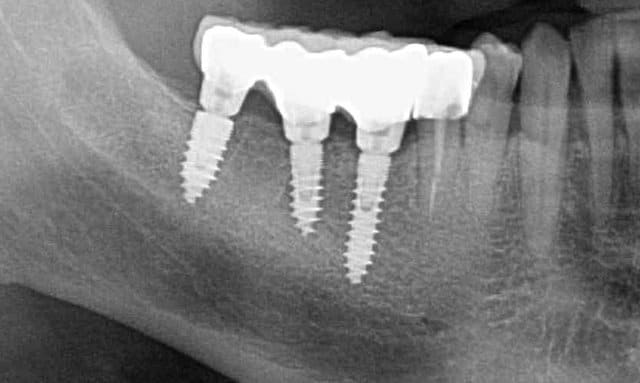

Pour ceux que ca interessent, et parce qu on a m a demandé des cas supplémentaires dans le sujet 23 implants rehabilitation totale, voici un autre cas d implantation immédiate avec la technique minimalement invasive et condensation grace aux forets.

Le patient a reçu un traitement il y a dix ans dans le maxillaire et dans le 4eme quadrant.Comme on peut le voir j´ai du extraire quelques dents au maxillaire: 35 37 et 45.

Le septum de la 37 a été foré avec un foret conique 3 faces.

J ai planté à 60 Ncm sans fracturer le septum.Juste après l opération , les prep caps en zircon ont été cémenté.La restauration définitive 34 jusqu` à 37 été fixé 2 semaines après l implantation avec implantlink (detax). Après un an, le bridge a été retiré facilement pour voir l´état de la gencive et faire une radio de contrôle.On la re ossifiction est satisfaisante et que la gencive "aime" le zircon.

Le bridge a ensuite été recémenté sans correction nécessaire du bridge.